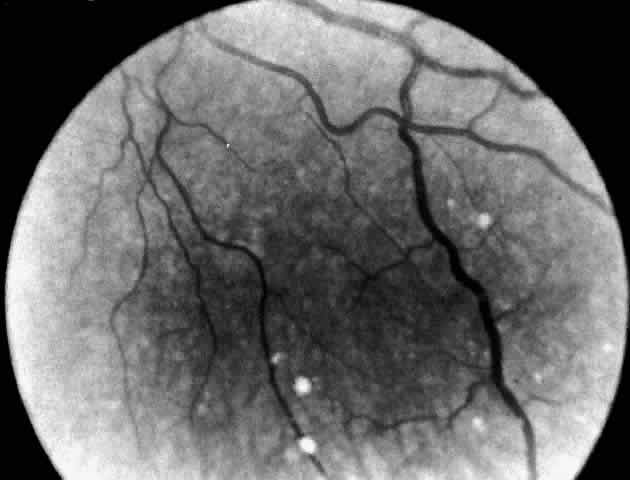

In three patients with type III subacute juvenile neuronopathic Gaucher's disease however, the retina showed a unique retinopathy. The findings in Cogan's case 1 are described: “Both fundi showed discrete white spots randomly distributed in the posterior fundus, especially along the inferior vascular arcades (Fig. 8). The spots varied in diameter from just visible to approximately 0.1 mm and were situated in the superficial retina or on the surface of the retina. Several covered the retinal vessels. The disc and retinal vessels were normal.” The child, an 11-year-old boy, had normal acuity and a full field of vision by confrontation. He had presented at age 3 years with splenomegaly.

Fig. 8. Fundus of a patient with type III subacute juvenile neuronopathic Gaucher"s disease showing discrete white spots in or on the retina along the inferior vascular arcades. At least one spot overlies a vein. The optic disc and retinal vessels were normal. (Cogan DG, Chu FC, Gittinger J, Tyshsen L: Fundal abnormalities of Gaucher"s disease. Arch Ophthalmol 98:2202, 1980. Copyright © 1980, American Medical Association)

Normal vision and similar retinal abnormalities were observed in a mildly mentally retarded 18-year-old woman (case 2) presenting with splenomegaly at age 1 year and in a 6½-year-old boy (case 3) noted to have hepatosplenomegaly in the first year of life. The patients in cases 1 and 3 had conspicuous supranuclear defects of eye movement.